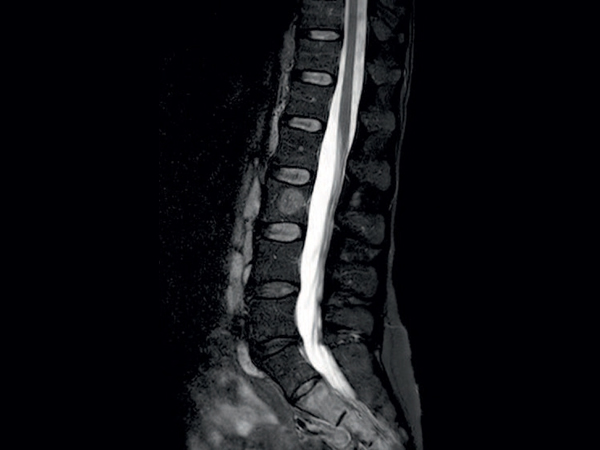

Comprehensive Lumbar Spine imaging at 1.5T

Meander Medical Center, Amersfoort, The Netherlands